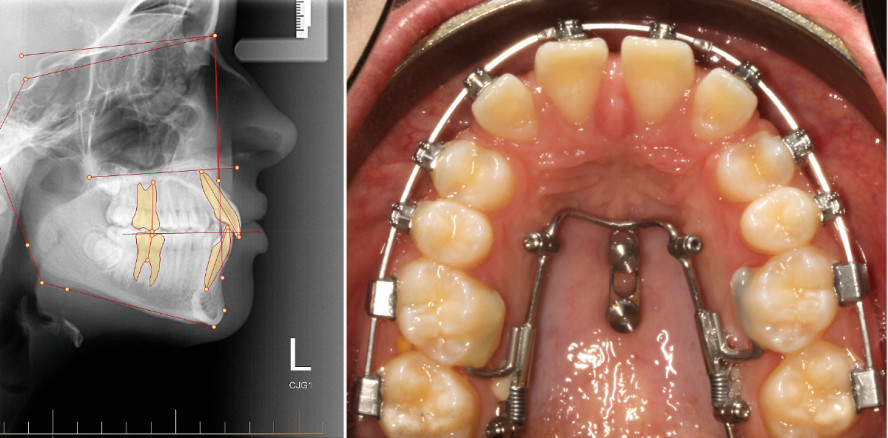

Bei einer 14-jährigen Klasse I-Patientin (mit Tendenz zu einer Angle-Klasse III) wurden extrem verlagerte obere Eckzähne diagnostiziert (Abb. 2a–k). Nach ausführlicher Risikoabwägung der Einordnung und Besprechung mit den Eltern und der Patientin sollten die oberen Eckzähne extrahiert und ein Lückenschluss nach mesial angestrebt werden. Als Alternativen wurde die prothetische Versorgung der Lücken diskutiert.

Nach erfolgter Digitalisierung der intraoralen Situation erfolgte die virtuelle Bracketpositionierung (Abb. 1a und b, Insignia™ System*). Mittels dieser sollte erstens eine optimale Okklusion eingestellt werden, des Weiteren aber auch eine besondere Positionierung der Brackets 14 und 24 erfolgen. Ziel war es, die ersten Prämolaren an die Stelle der Eckzähne zu stellen. Damit es zu einem harmonischen Gingivaverlauf kommt, wurden die Zähne 14 und 24 in eine ausgeprägte Infraposition gesetzt. Nach Bestätigung durch den Behandler wurden die Übertragungstrays für das indirekte Kleben der Brackets hergestellt. Die Brackets wurden anschließend geklebt und die Zahnbögen über fünf Monate bis zu einem .016'' x .025'' Vierkantbogen nivelliert.

Nach einer Gesamtbehandlungsdauer von 23 Monaten wurden alle Brackets entfernt (Abb. 8a–f), um anschließend die Zähne 14 und 24 mit Kompositaufbauten umzugestalten (Abb. 9a–j). Die Zähne 11 und 21 wurden mit Veneers verbreitert. In der Überlagerung der Fernröntgenseitenaufnahmen erkennt man die Oberkiefer-SeitenzahnMesialisierung ohne einen Verankerungsverlust im Sinne einer ungewünschten Retrusion der Ober- und Unterkiefer-Frontzähne (Abb. 10 und Tabelle 1).